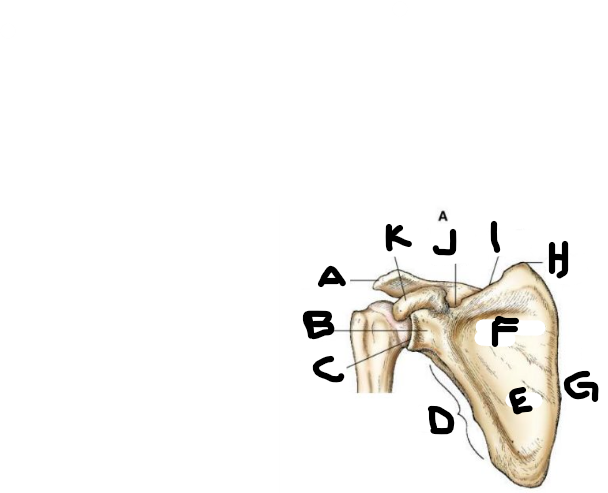

posterior scapula A

supraspinous fossa

posterior scapula B

infraspinous fossa

posterior scapula C

lateral border

posterior scapula D

lateral angle

posterior scapula E

neck

posterior scapula F

glenoid cavity

posterior scapula G

acromion

posterior scapula H

coracoid process

posterior scapula I

scapular notch

posterior scapula J

superior border

posterior scapula K

superior angle

posterior scapula L

crest of spine

posterior scapula M

medial border

posterior scapula N

inferior angle

anterior scapula A

anterior scapula B

anterior scapula C

anterior scapula D

anterior scapula E

body

anterior scapula F

subscapular fossa

anterior scapula G

anterior scapula H

anterior scapula I

anterior scapula J

anterior scapula K